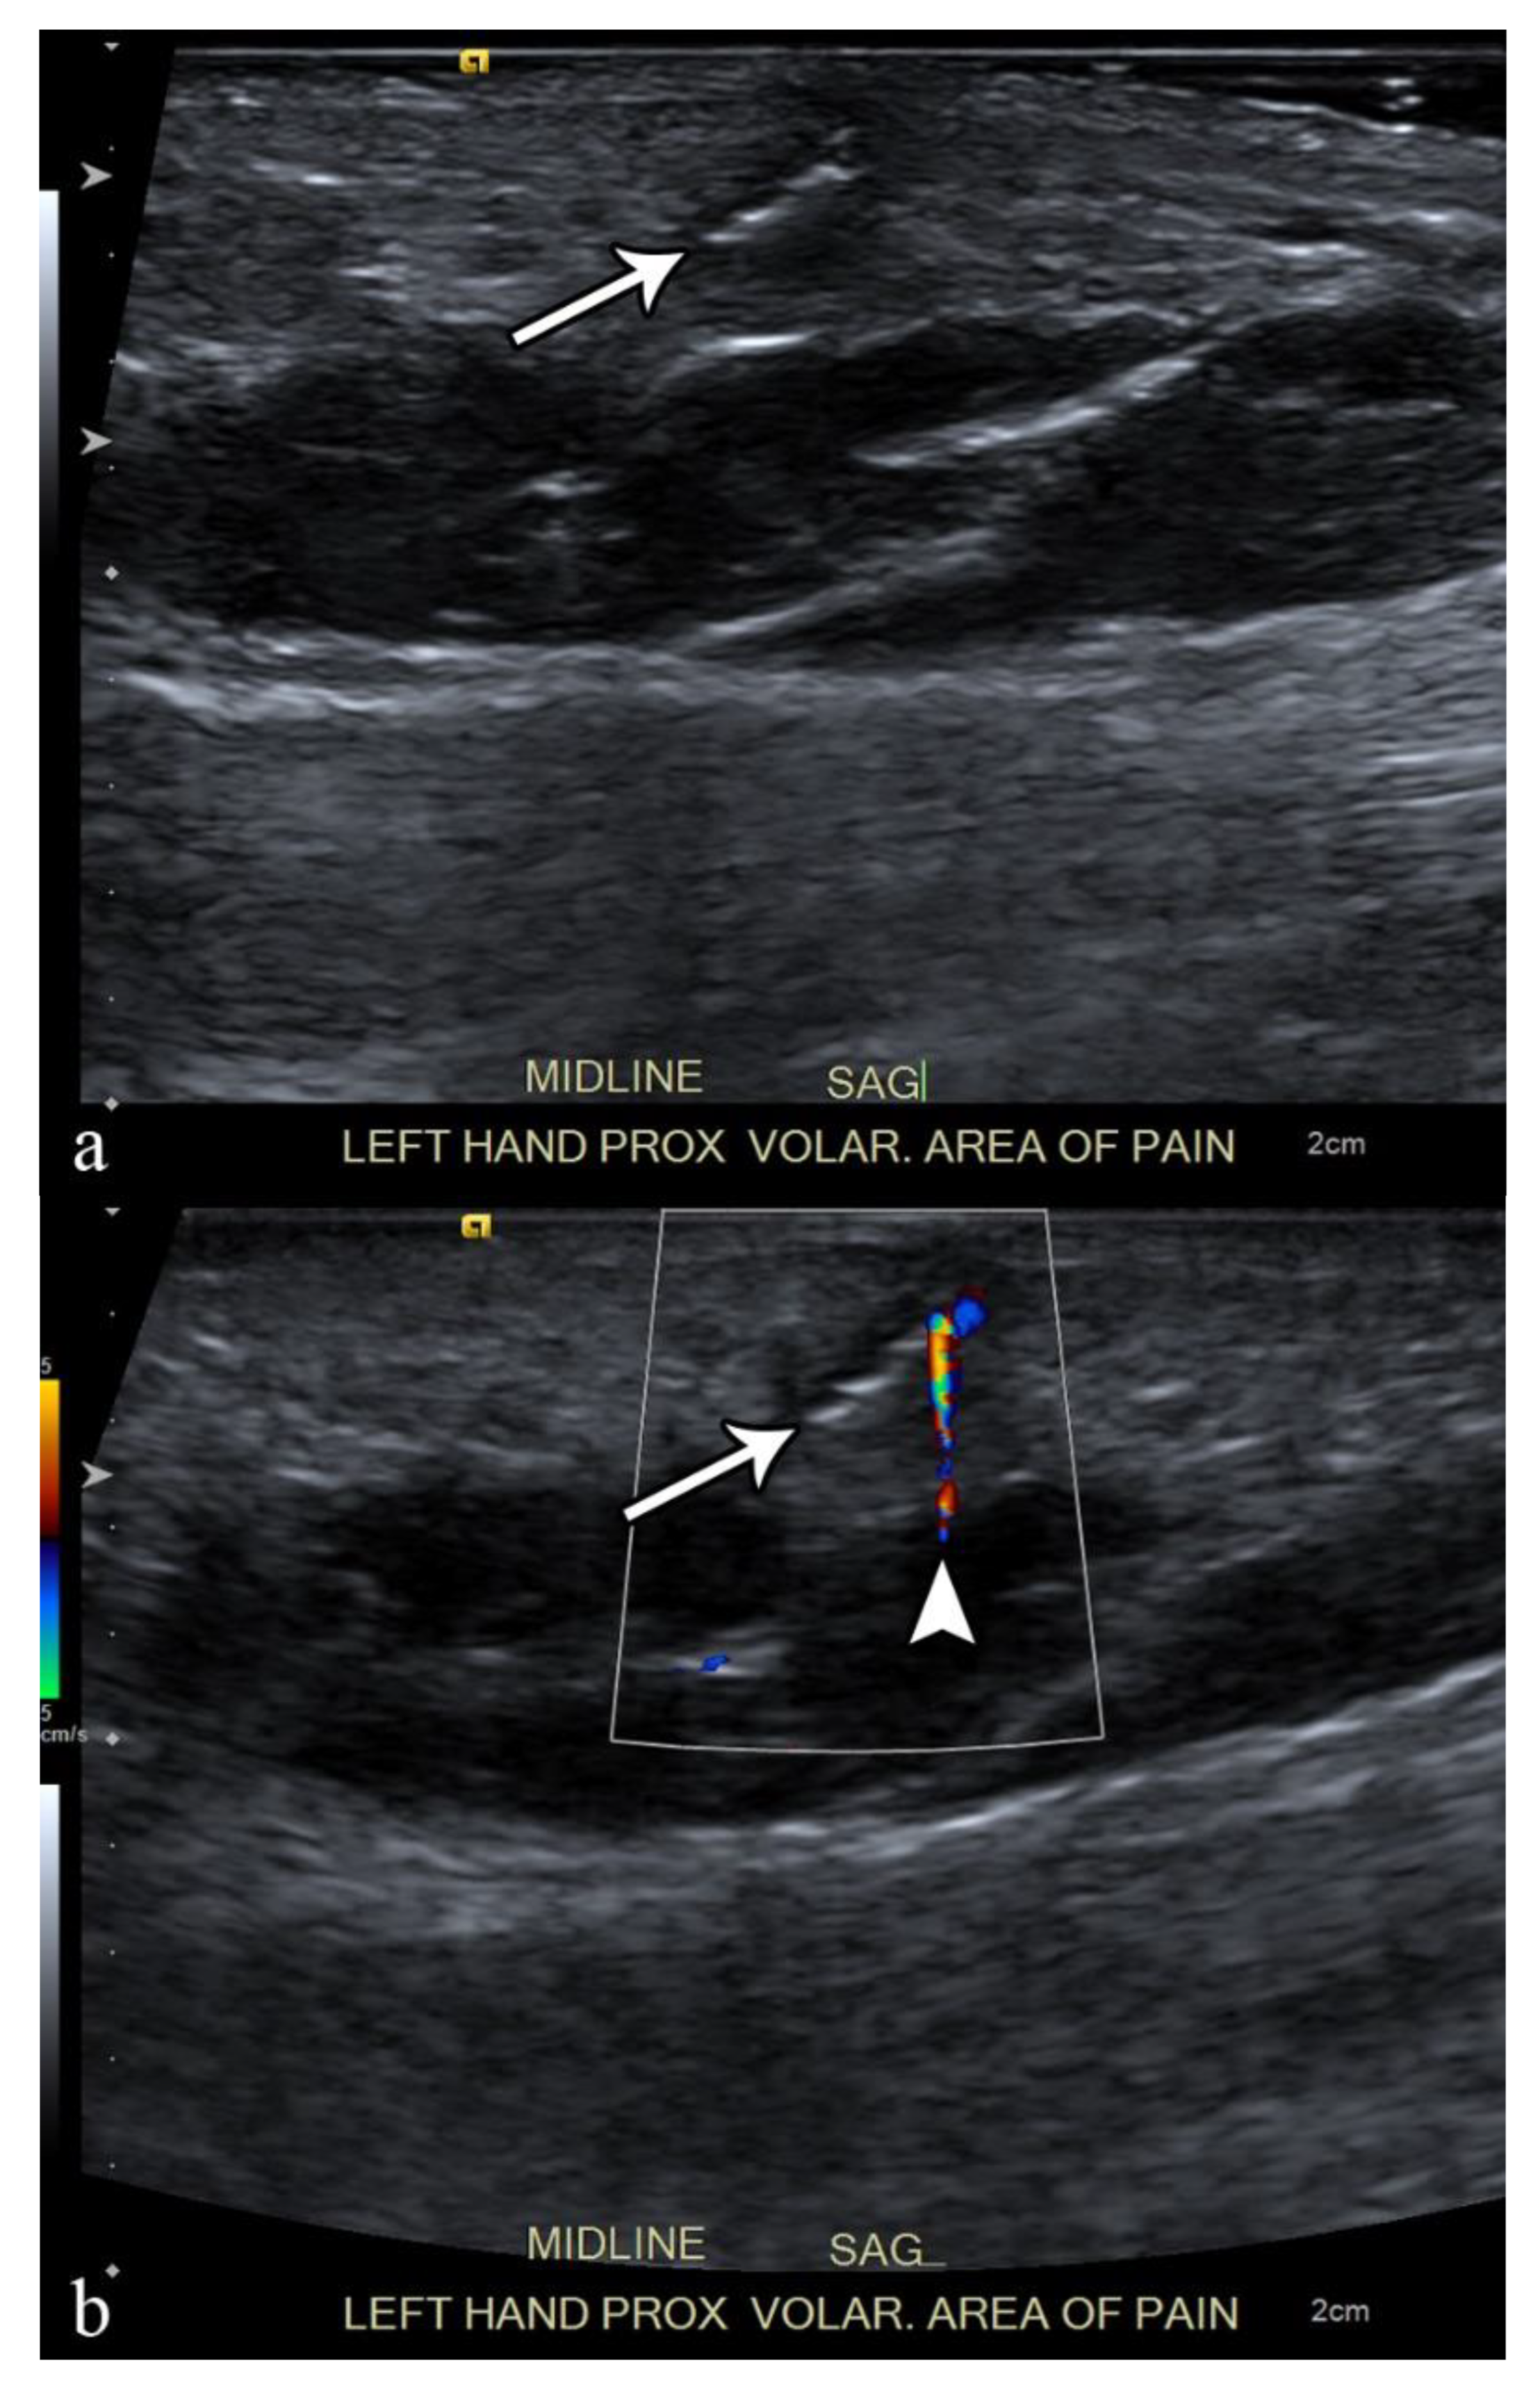

2.2. Necrotizing and Non-Necrotizing Fascitiis

| US | • Increased echogenicity and thickening of subcutaneous soft tissue • Fluid tracking along the fascia • Gas seen as echogenic foci with dirty posterior acoustic shadowing |

| MRI | • Thickening of deep fascia ≥ 3 mm • Fluid extending deep along intermuscular fascial planes • Involvement of more than 3 compartments • Variable enhancement with areas of fascial enhancement (inflammation) and lack thereof (necrosis) • Gas seen as foci of signal void on all sequences • May be band like edema/enhancement in periphery of muscles |